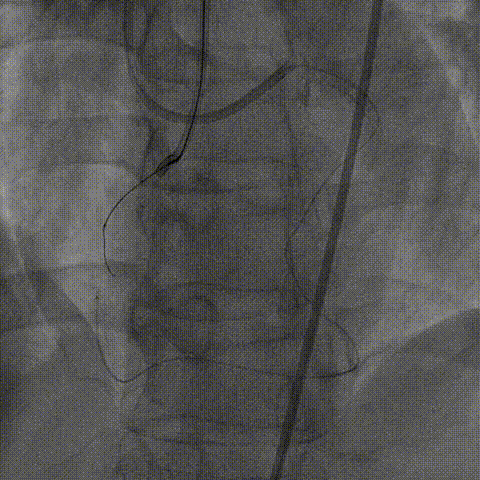

器械通过困难:

1、正向导丝通过后,微导管无法跟进,尝试1.25、1.5mm球囊均无法通过病变。

2、6F Telescope™导引延长导管支撑下1.25mm球囊通过病变预扩后换用2.0mm球囊完成预扩张。

右冠PCI

1、2.0mm球囊预扩张后球囊顺利进入Telescope™导引延长导管锚定导丝,送入Finecross微导管,后交换Pilot200导丝为Runthrough导丝。

2、6F Telescope™导引延长导管可兼容2号2.0mm预扩球囊及Finecross微导管同时进入,具有良好的内腔兼容性。

2.0mm球囊进入Telescope™锚定,通过无阻力

2.0mm球囊锚定导丝后微导管进入Telescope™内腔兼容性强

1、2.0mm顺应性球囊预扩后,Telescope™支撑下火山血管内超声(头端直径较大)无法通过,操作过程中右冠系统脱出,重新放置右冠指引管后在逆向导丝指引下正向导丝再次通过病变至右冠远端。

2、换用2.75非顺应性球囊在Telescope™支撑下扩张闭塞段并引导Telescope™通过闭塞段后完成血管内超声检查。

内腔同时兼容2.0mm球囊及Finecross微导管